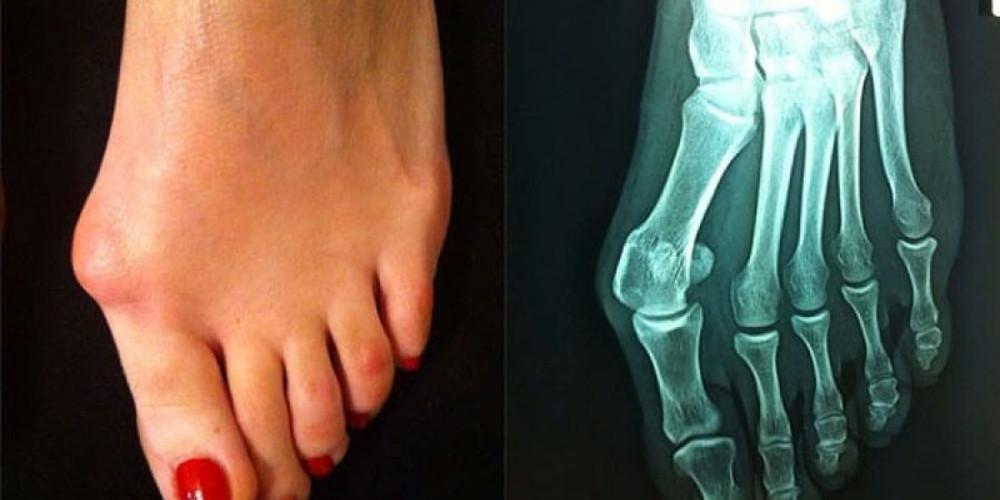

Η παραμόρφωση που δημιουργεί το κότσι στο μεγάλο δάκτυλο του ποδιού και οι εξελκώσεις, δυσκολεύουν ιδιαίτερα τη βάδιση καταπονώντας έτσι συνολικά τις αρθρώσεις σας. Όμως, παρά το γεγονός ότι υπάρχουν περισσότερες από 120 διαφορετικές τεχνικές για την αποκατάστασή του προβλήματος ελάχιστες γυναίκες αποφασίζουν να χειρουργηθούν με το φόβο ότι ο μετεγχειρητικός πόνος θα είναι έντονος. Με τις σημερινές τεχνικές όμως αυτό δεν ισχύει.

Το 70% των ασθενών που χειρουργούνται από κότσι έχουν οικογενειακό ιστορικό αν και τα στατιστικά στοιχεία δείχνουν ότι η νόσος που προκαλεί το κότσι θεωρείται επίκτητη και όχι συγγενής. Η ασθένεια είναι μάλλον «γυναικεία υπόθεση», αφού τα κομψά ψηλοτάκουνα παπούτσια, ενοχοποιούνται ως αιτία πρόκλησης κι επιδείνωσης της συγκεκριμένης παραμόρφωσης. Τα ποσοστά άλλωστε μιλούν από μόνα τους αφού η αναλογία γυναικών- ανδρών είναι 9 προς 1. Άλλες αιτίες της νόσου είναι οι αυτοάνοσες παθήσεις (ρευματοειδής αρθρίτιδα), οι νευρογενείς διαταραχές, η ανισορροπία της εμβιομηχανικής του ποδιού κ.ά. Πρόκειται για μια σύνθετη παραμόρφωση της πρώτης άρθρωσης (μεταταρσοφαλαγγικής) του μεγάλου δακτύλου του ποδιού. Η παραμόρφωση αυτή δημιουργεί βλαισότητα και στροφή του μεγάλου δακτύλου, ως προς τον άξονά του.

Συγκεκριμένα στο εσωτερικό τμήμα της άρθρωσης αυτής, δημιουργείται μία προπέτεια (κάλος). Η φυσική εξέλιξη της νόσου είναι η παρέκκλιση του μεγάλου δακτύλου προς το δεύτερο ή και τρίτο δάχτυλο, τα οποία παραμορφώνονται με σφυροδακτυλία, γαμψοδακτυλία ή εφίππευση πάνω στο μεγάλο δάχτυλο. Επίσης δημιουργούνται κάλοι στα δάχτυλα αυτά.